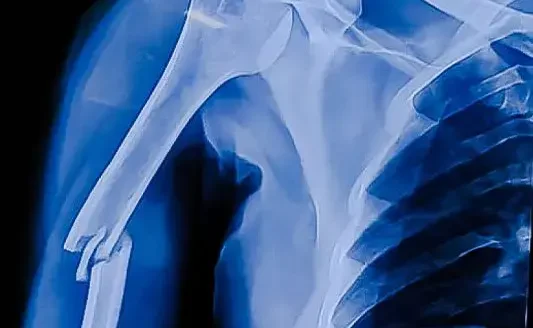

5. Karmaşık Fraktür

Bu tür fraktürlerde, kemik birden fazla yerden kırılır ve parçalar halinde dağılır. Bu tür durumlar genellikle cerrahi müdahale gerektirir.

2. Cerrahi Müdahale

Komplike kırıklar, parçalanmış kemikler veya açık kırıklar cerrahi müdahale gerektirebilir. Cerrahi işlem sırasında kırık kemikler tekrar yerleştirilir ve genellikle vida, plaka veya çivilerle sabitlenir.